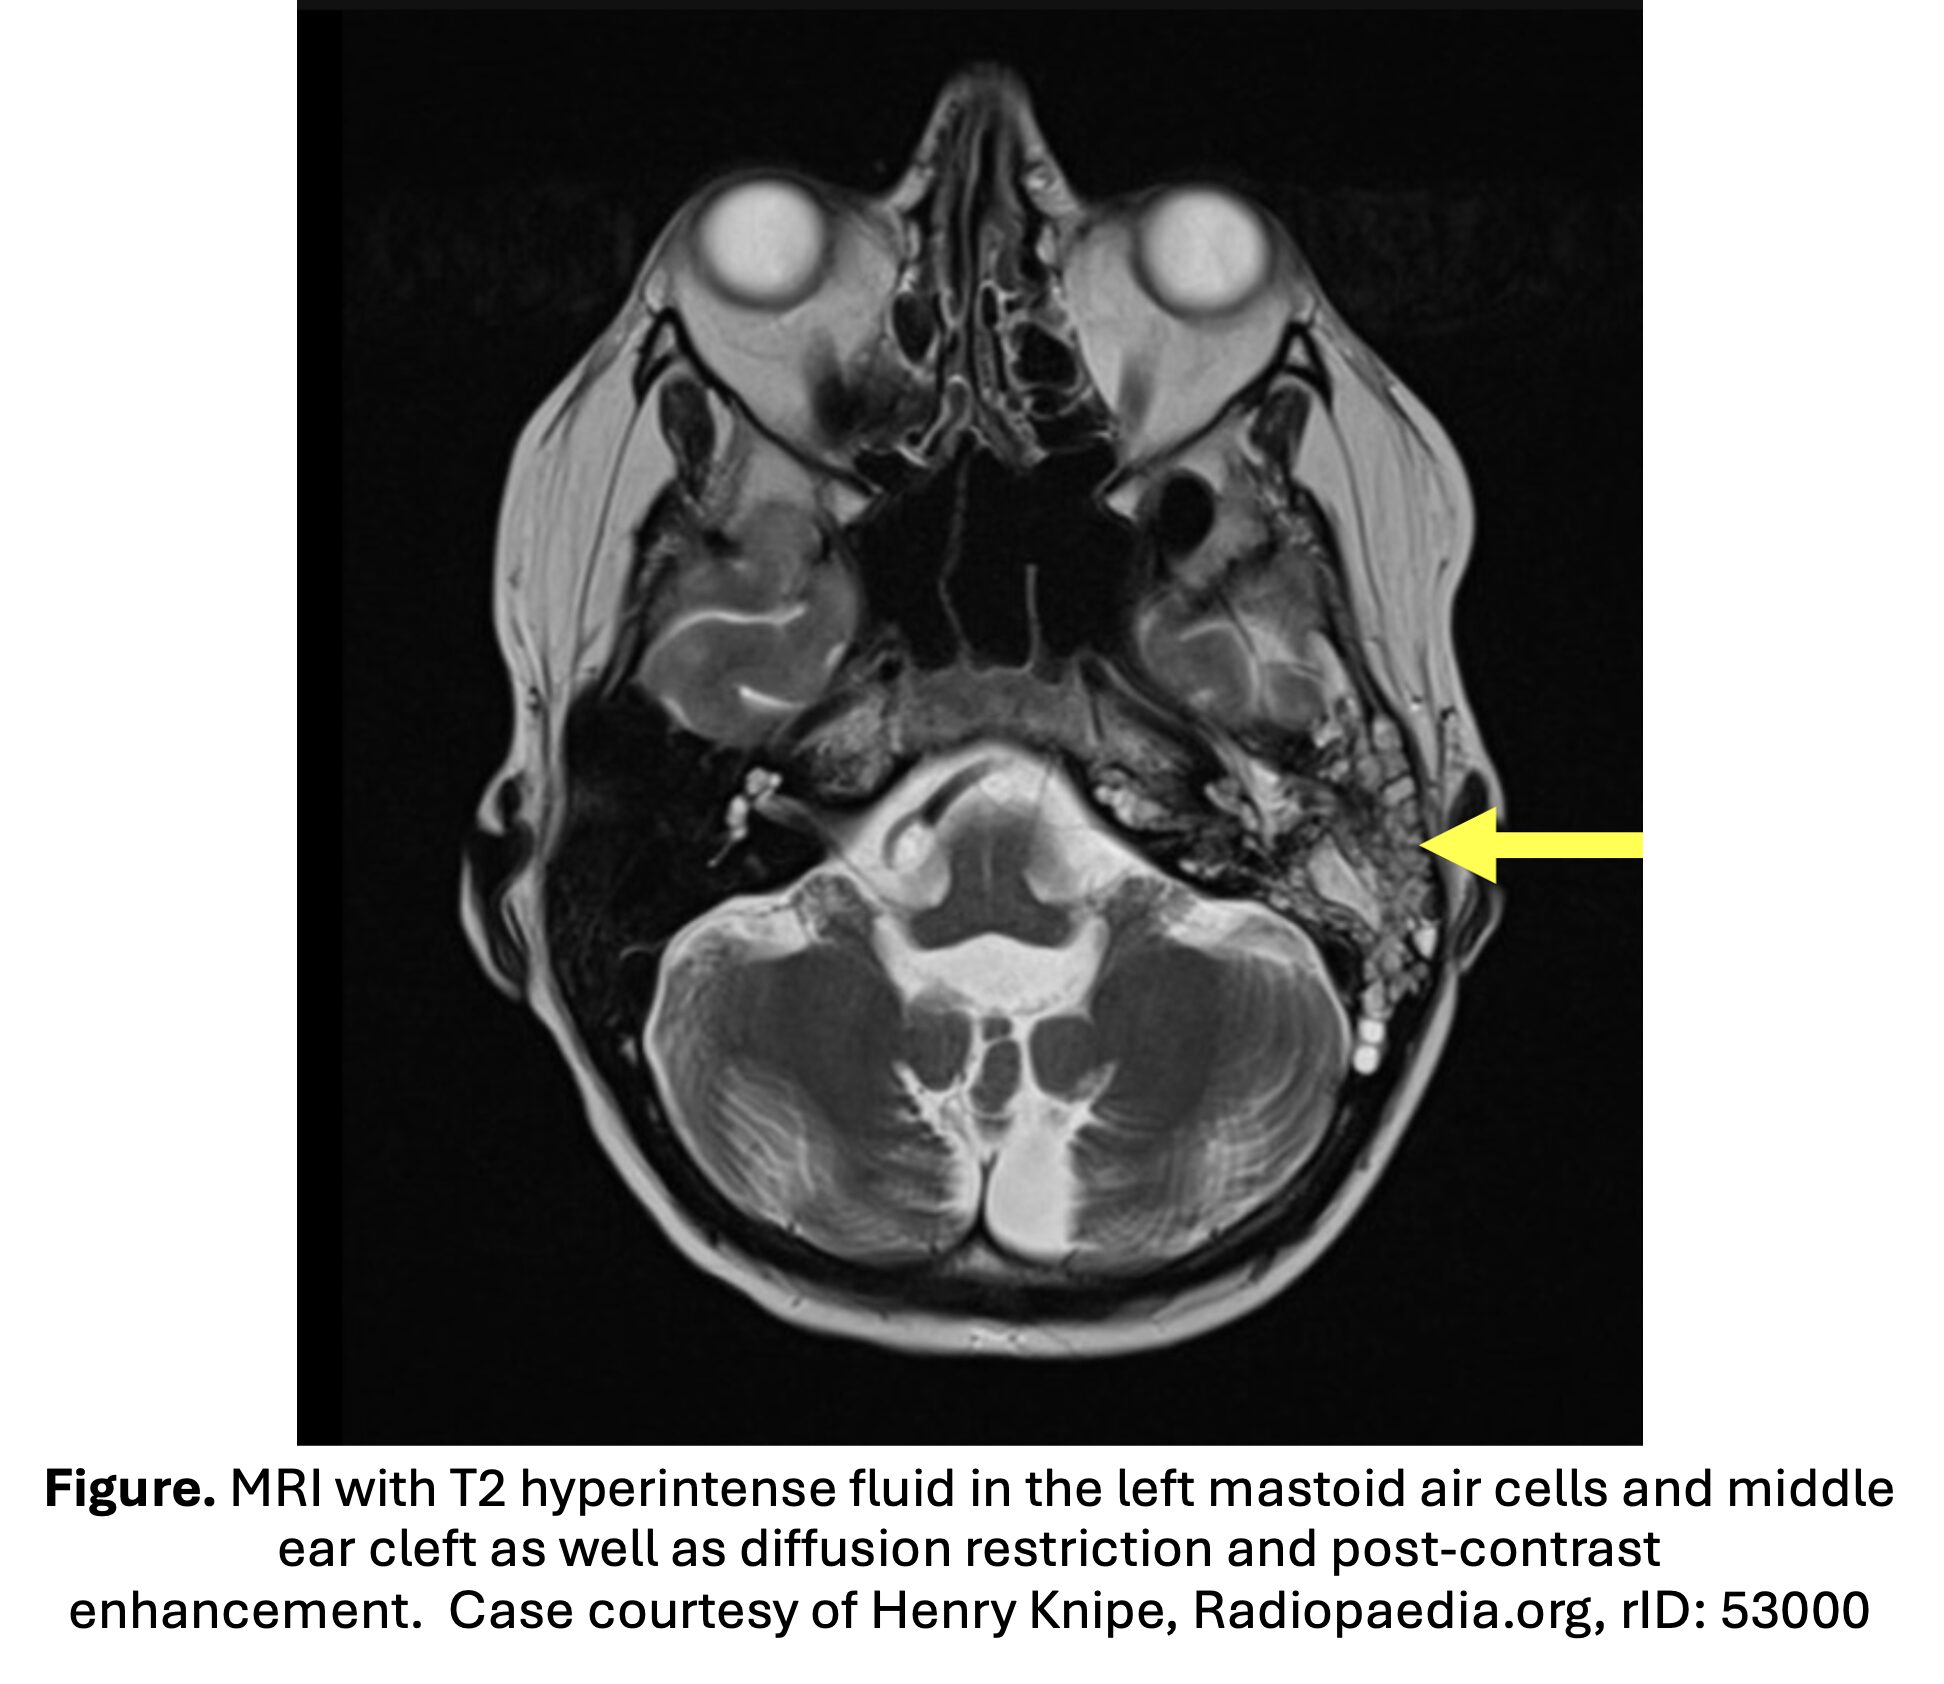

• Second line imaging modality: MRI with gadolinium contrast.

• Higher sensitivity for extra-axial fluid collections compared to CT; can evaluate intracranial structures and vascular complications (Vazquez).

• MRI may be pursued if concern for intracranial or vascular complication, IV contrast allergy, or in pediatric patients to avoid radiation exposure if MRI available.